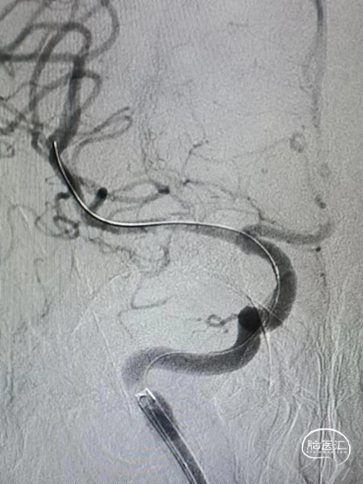

治疗中影像

Guiding到位,导丝通过病变。

球囊通过病变。

球囊扩张过程。

扩张后造影。

支架通过病变。

支架释放。